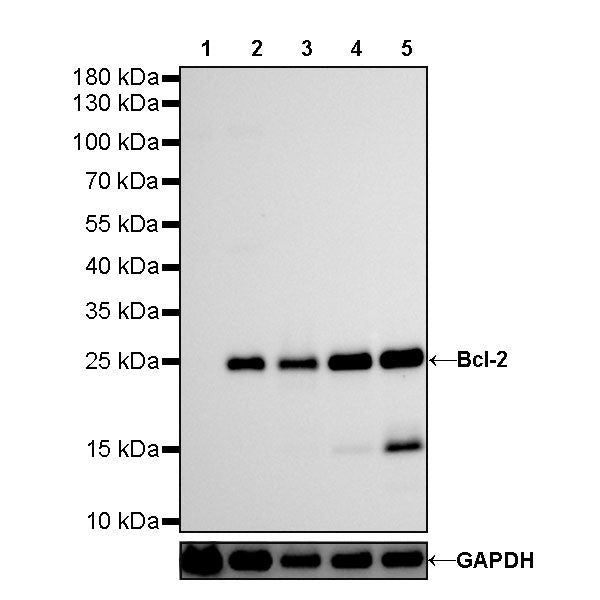

Western Blot